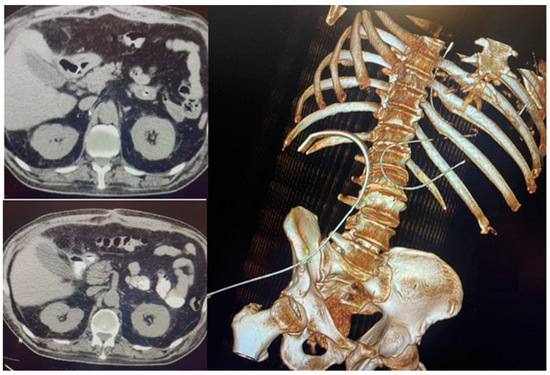

An abdominal-pelvic native CT was performed, which revealed a voluminous collection of mixed hydro-aerial contents and radio-opaque material (an orally administered contrast substance) located in the subphrenic region, extending along the anterior abdominal wall to the supraumbilical region with global dimensions of 98/314/178 mm (AP/T/CC), and was well-defined. A contrasting substance was also present in the GI tract distal to the perforation. Elevation of the right hemi-diaphragm was identified with an overlying lamellar atelectasis. An approximately 19 mm parietal defect was found at the level of the duodenal bulb, with a wide communication along a 100 mm long fistulous tract and a collection adjacent to the gallbladder inferiorly. Peritoneal air bubbles were also present adjacent to the collection. The liver dimensions were increased (right lobe of 183 mm and left lobe of 75 mm anterior-posterior incidence) with a homogenous structure, no dilated extra and intrahepatic biliary ducts, a gallbladder with liquid content with normal wall thickness without radiopaque calculi, a normal permeable portal venous system, and a normal pancreas and suprarenal glands. The spleen dimensions were approximately 132/50/111 mm with a homogenous structure, the kidneys were at the normal positions and had normal dimensions and secretions, and the right superior polar cortical cyst was 8 mm in diameter, with 12 mm lamella of perisplenic fluid an infiltrated aspect of peritoneal fat, a collapsed stomach, and a colon without preparation and without parietal modifications regarding the caliber of a normal size. There was bilateral pleural fluid: 23 mm on the right and 13 mm on the left. There was left basal calcareous pachypleuritis. The urinary bladder was in semirepletion, and the prostate had normal dimensions. The conclusion was a duodenal-covered perforation, subphrenic fistula, and voluminous subphrenic collection predominately full of air and a small quantity of pneumoperitoneum.

We performed an abdominal-pelvic CT scan, which revealed the closure of the perforation with the absence of extravasation from the gastrointestinal tract of the orally administered contrast. The contrast was present in the jejunum. The right subphrenic collection dimensions were reduced, with mixed air/liquid content at a maximum of 25 mm. At the level of the perforation, anteriorly describes the aspects of a pseudodiverticulum (length 20 mm, permeable lumen 7 mm), which associates with discrete infiltrates of adjacent fat. Bilateral pleural liquid with a thickness of 36 mm on the right and 33 mm on the left was present, with passive atelectasis of the underlying lungs and bilateral basal fibrosis bands [Figure 3].

Figure 3.

Absence of extravasation from the gastrointestinal tract of the contrast substance.